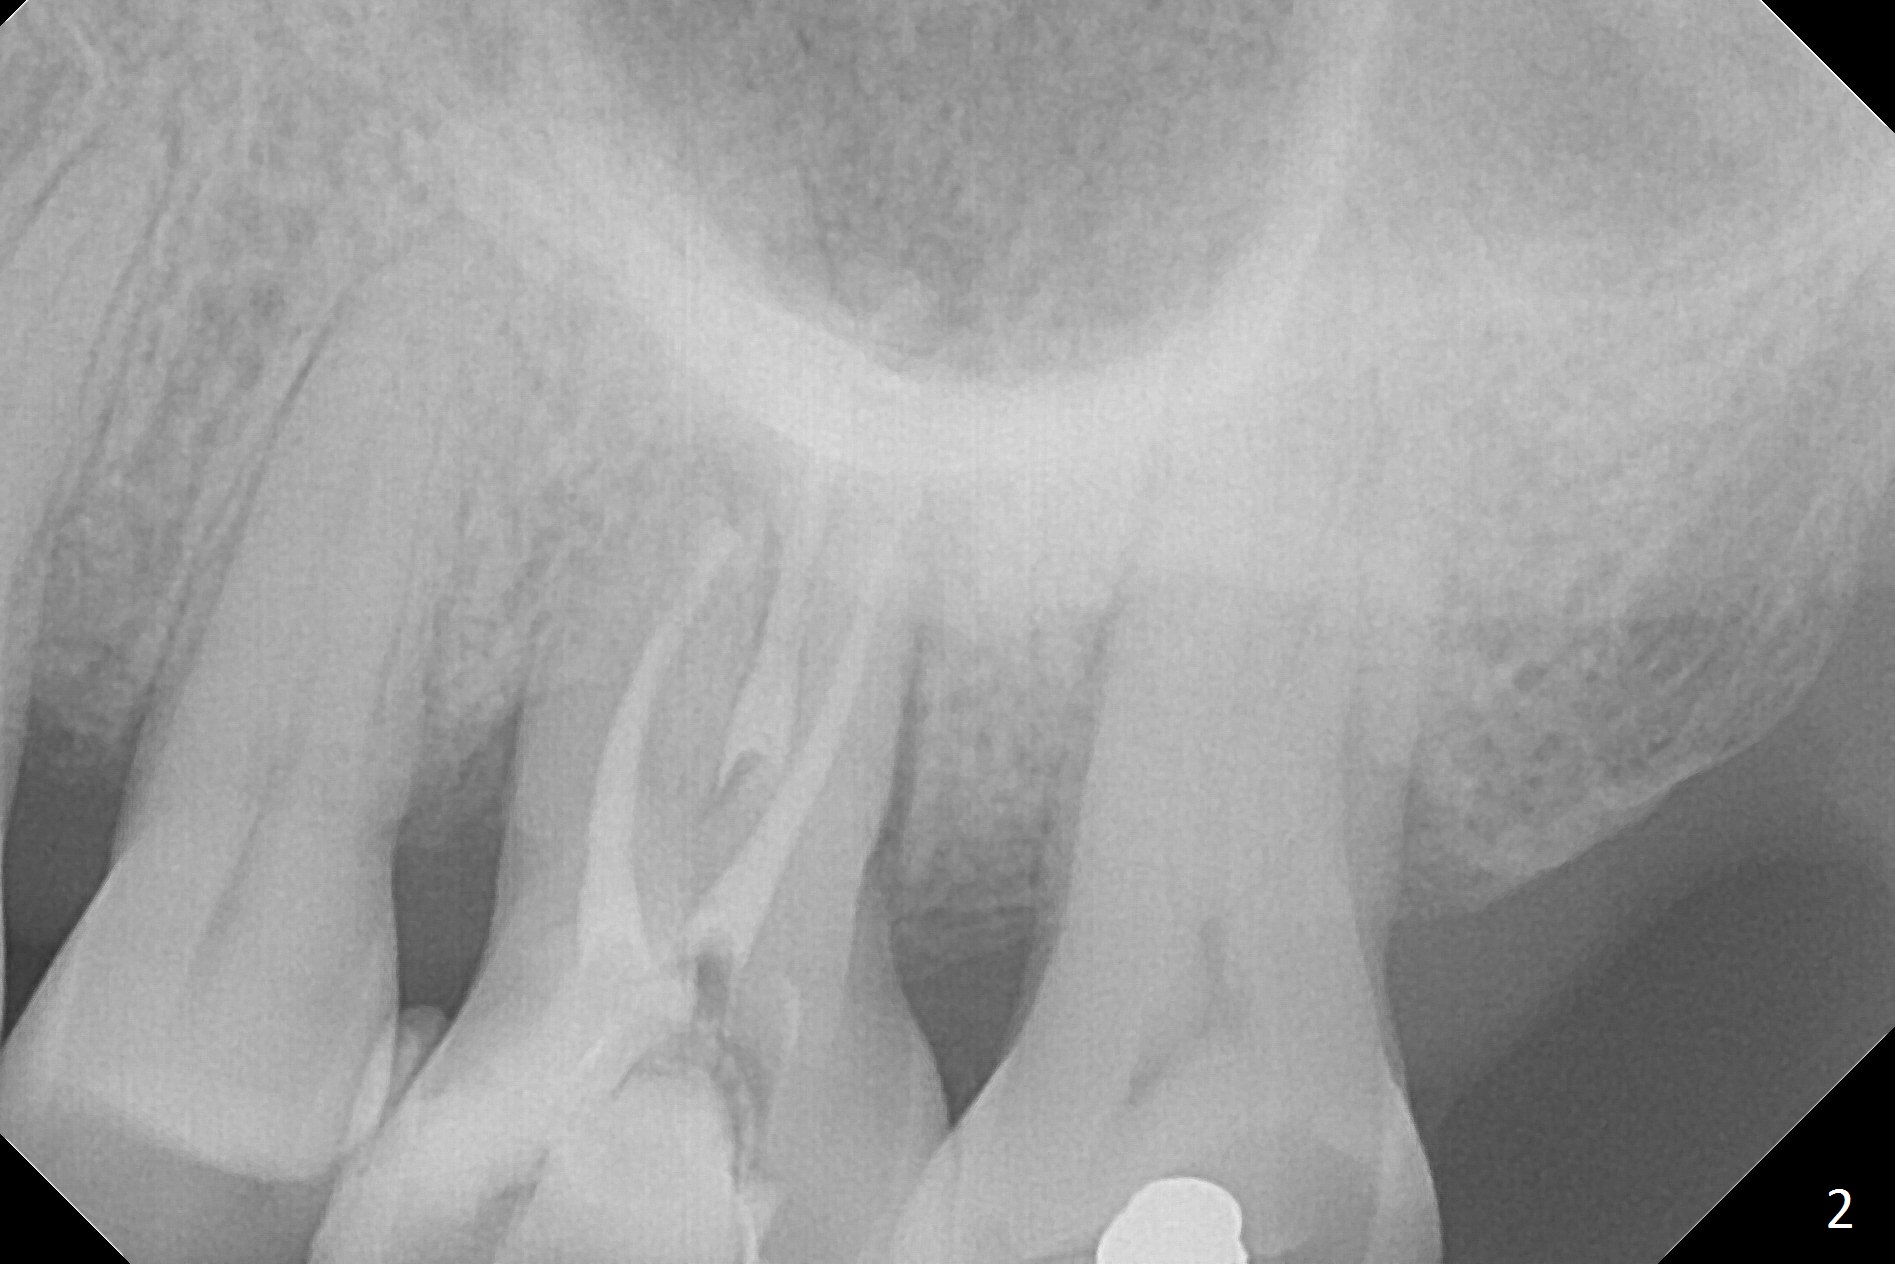

A 70-year-old woman has pain at MB root area post RCT at #14 (Fig.1,2). The tooth seems to have endo-perio disease (bone loss with gingival recession at MB) and be non-salvageable. After extraction and Metronidazole treatment, start osteotomy with 1.6 mm drill 1-2 mm shy of the sinus floor, followed by PA. Use Lindamann bur for ostetoomy position and trajectory adjustment. Use Marking Bur if necessary before Magic Drill 4.3 mm if the septum is wide. The depth of the osteotomy is 1-2 mm coronal to the sinus floor. Do not use the final drill, i.e., saving the osteotomy plug in place. Next 4.5x11 mm dummy implant is placed to push the plug upward for lifting. Place an implant as large as possible, but not violating the buccal gap (Fig.3).

The patient must be a bruxer, since the roots of the tooth #15 is long (Fig.1). The immediate provisional should have occlusal clearance.